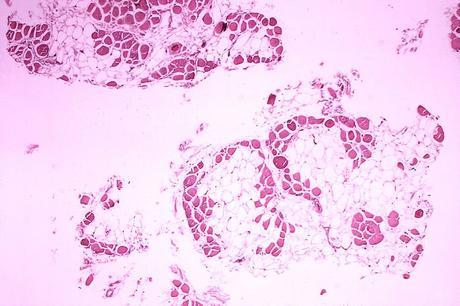

Distrofia muscular de Duchenne es una enfermedad muscular degenerativa hereditaria que progresa rápidamente en comparación con otras enfermedades musculares. La enfermedad se llama así por Guillaume Benjamin Duchenne, un neurólogo francés que lo descubrió en 1861. DMD es causada por una mutación en el gen de la distrofina que es responsable de la conexión de la fibra muscular a la matriz celular a través de un complejo específico de proteínas. La ausencia de distrofina evita que el exceso de calcio se absorba adecuadamente en la membrana celular, lo que causa daño, atrofia y necrosis del tejido muscular.

- Deformación de la fibra muscular